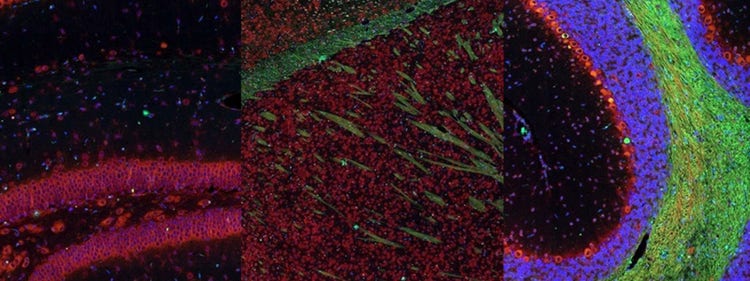

Fluorescence imaging of a mouse brain

각 확대 이미지는 특이해 보이지만, 모두 모아보면 형광 이미징으로 촬영한 생쥐 뇌가 나타납니다.

영국 과학자 George G. Stokes 경은 형석에 자외선을 비추면 형광을 발한다는 사실을 처음으로 목격했고, ‘형광’이라는 단어를 만들어냈습니다. Stokes 경은 형광 광원이 여기광원보다 파장이 더 길다는 사실을 발견했으며, 이 현상은 현재 스토크스 이동으로 알려져 있습니다. 형광 현미경은 자연적인 형태(일차 형광 또는 자가형광)이거나 형광을 발할 수 있는 화학물질로 처리했을 때 형광(이차 형광)을 발할 수 있는 물질을 연구하는 탁월한 방법입니다.